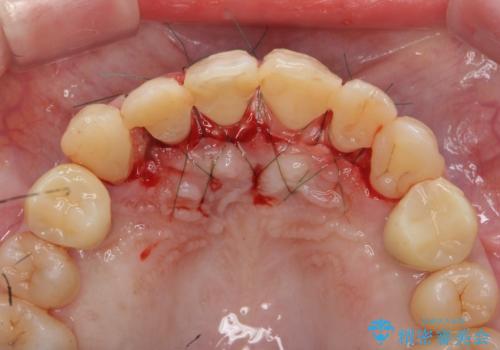

まず虫歯を拡大鏡、マイクロスコープ下で丁寧に取り除き歯肉縁下の虫歯を歯周外科により解決したのち、ジルコニアクラウン製作を行っていきます。

丁寧な虫歯の除去・歯周組織の整備、適合の良い精密なセラミッククラウンの製作といった丁寧な治療の積み重ねが良好な治療結果を得ることにつながります。